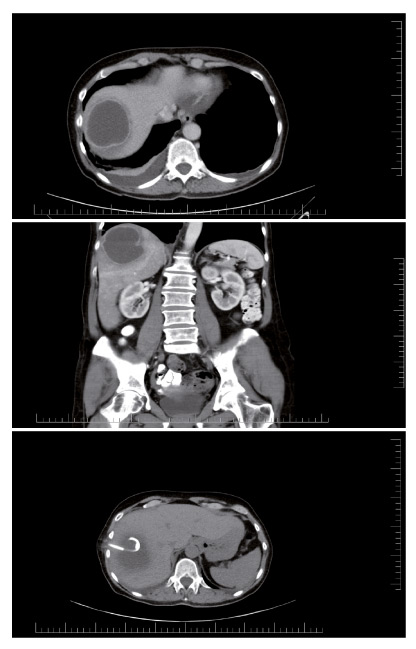

Po překladu na KIN byla pacientce zavedena intravenózní terapie kombinací antibiotik a bylo přizváno chirurgické konzilium k zvážení provedení perkutánní drenáže. U pacientky byla sérologicky potvrzená amébová etiologie. V průběhu hospitalizace došlo ke zhoršení zdravotního stavu pacientky, měla především bolesti v pravém podžebří, nechutenství a celkovou slabost. Na začátku dubna byla provedena pod CT kontrolou navigovaná punkce jater se zavedením drenáže obou tekutinových kolekcí jater (obr. 1–3). Podtlakové drény odváděly velmi hustou tekutinu charakteru ančovičkové pasty. Kontrolní ultrazvukové vyšetření pravého podžebří potvrdilo reziduální abscesové ložisko v pravém laloku s kolekcí tekutiny a v levém laloku ložisko menší, bez zjevné kolekce tekutiny. Další kontrolní ultrazvukové vyšetření jater neprokázalo progresi nálezu, v okolí obou drénů nebyla zjištěna volná tekutina a byla provedena extrakce obou drénů.

Obr. 1 amébový absces jater, ct břicha, transverzální řez.

Obr. 2 amébový absces jater, ct břicha, koronární řez.

Obr. 3 amébový absces jater, ct břicha, transverzální řez. patrný je zavedený drén. regrese velikosti abscesu.